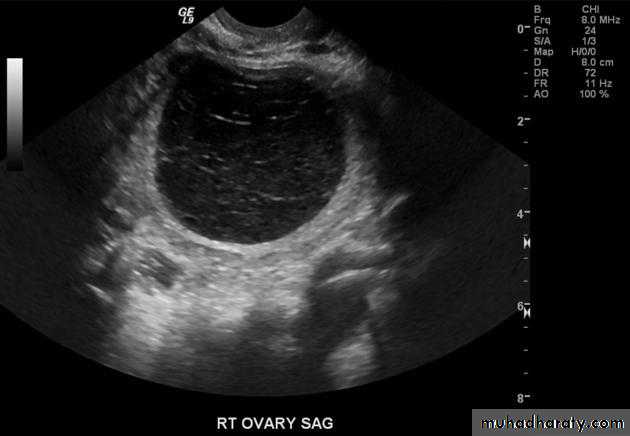

Ovarian cysts

Ovarian cysts are commonly encountered in gynecological imaging, and vary widely in etiology, from physiologic, to complex benign, to neoplastic.

Small cystic ovarian structures should be considered normal ovarian follicles unless the patient is pre-pubertal, post-menopausal, pregnant, or the mean diameter is >3.0 cm

Radiographic features

Ultrasound is usually the first imaging modality for assessment of ovarian lesions. Simple ovarian follicular cysts are:

anechoic

intraovarian or exophytic;

have an imperceptible wall